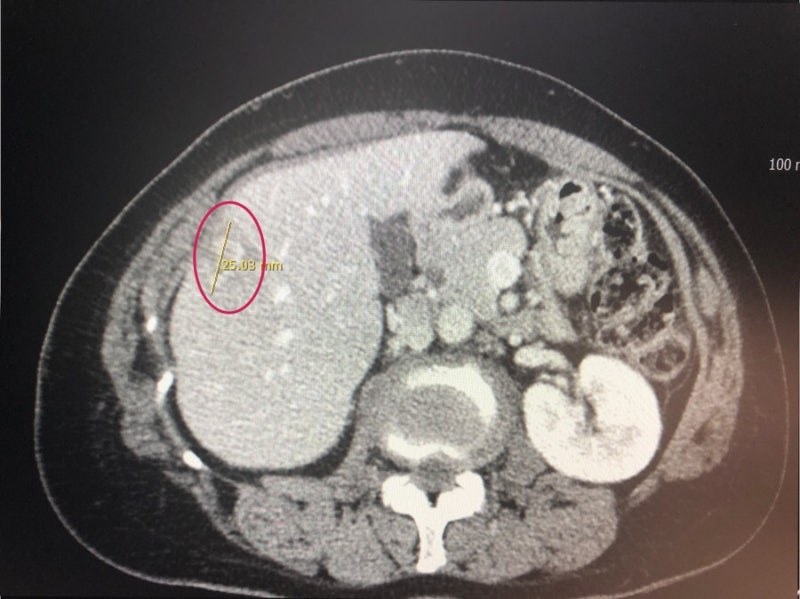

유방은 남녀 모두 있지만 여성의 유방은 사춘기부터 발달하고 각종 호르몬 작용과 모유를 생산하는 기능을 합니다.이런 여성의 유방에서 암세포가 발생한 것을 유방 암이라고 합니다유방 암의 원인에는 여성 호르몬 문제나 방사선의 많은 노출 외에도 식사 습관, 흡연 음주 환경 호르몬 등의 위험 요인으로 보고됐고, 가족력이 높은 유방 암 발병률을 나타내는 유전적 요소도 크게 작용하는 것으로 보고되고 있습니다.유방 암은 1기에는 90~100%정도의 높은 생존율을 보이지만, 유방 암 말기의 4기는 20~30%의 매우 낮은 생존율이라고 보고되어 생명을 위협하게 됩니다.유방 암 말기는 유방의 암세포가 다른 장기로 전이된 상태를 의미합니다만, 유방 암의 골 전이 증상으로 유방 암의 간질/유방 암의 간질 전이, 유방 암 폐 전이까지 다른 장기로의 전이가 발생하는 경우가 많고, 무기 관리가 매우 중요합니다.오늘은 유방 암의 골 전이 증상으로 유방 암 줄기 전이 증상 등 전이에 따른 증세와 유방 암 말기 등 예후를 높이기 위한 소재까지 소개합니다.

유방 암의 초기에는 아무런 증상도 없이 우연의 검진과 유방 암 말기로 이어질 때 뚜렷한 증상이 발생하는 것도 있지만 대표적으로 응어리가 닿거나 유두 분비물/젖꼭지의 고치기 어렵게 습진의 모습도 나타날 수 있습니다.유방 암 말기 증세로 유두가 유방의 안쪽에 침울한 증상이나 통증 체중 감소 등의 발생이 있습니다유방 암은 전이 부위에 의해서 생존율과 증상이 달라질 수 있습니다유방 암의 골 전이 증상의 경우 뼈가 척추를 누르고 통증과 행동 제한이 생긴다, 뼈가 약해지고 골절 하고 부러질 유방 암의 골 전이 증상이 나타날 수 있습니다.유방 암 폐 전이의 경우 호흡 곤란 및 각혈, 기침, 폐 출혈 등의 유방 암 폐 전이 증상이 있습니다.유방 암 튀김의 경우는 두통이나 인지 저하, 근육 경직 난청이나 경련 구역 구토 등의 유방 암 튀김의 증세가 있어요 마지막으로 유방 암 줄기 전이에는 발열과 무기력, 식욕 부진, 체중 감소, 드문 간이 커지고 복부 팽창 등의 유방 암 줄기 전이 증상이 발생할 수 있습니다.유방 암의 재발률은 20~30%에 해당하는 만큼 초기 발견에도 유방 암의 재발에 의해서 여러 장기 몸에 대한 전이가 발생하고 높은 무기에 진행되고 생명을 위협하는 것도 있습니다.그러나 반대로 유방 암 말기 유방 암이 다른 곳으로 전이된 상태에서도 완치하는 사례도 잘 있어 환자의 재발과 전이 등을 관리의 정기적인 추적 관찰과 향후의 병기 개선을 위한 예후 관리가 중요합니다 많은 예후에 대해서 음식이 있었는데 이곳에서는 많은 논문을 통해서 세계적으로 주목 받고 있는 말굽 버섯을 준비했습니다.